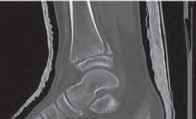

Rycina 17.82.

Uszkodzenie tętnicy podkolanowej wskutek złuszczenia nasady bliższej kości piszczelowej (S-H 1). Zagrożenie rozwojem zespołu przedziałów powięziowych jest poważne.

Rozpoznanie

Objawy złamania to silny ból uniemożliwiający stanie i chodzenie, zniekształcenie obrysów stawu kolanowego przez krwiak i różnego stopnia przemieszczenie nasady kości piszczelowej. Należy dokładnie zbadać stan ukrwienia i unaczynienia kończyny pod kątem objawów uszkodzenia tętnicy podkolanowej i nerwu strzałkowego. Trzeba ocenić bolesność uciskową oraz napięcie w przedziałach powięziowych podudzia: przednim, bocznym, tylnym powierzchownym i tylnym głębokim. U pacjentów z podejrzeniem wzmożonego ciśnienia wewnątrzprzedziałowego należy wielokrotnie powtarzać badanie ukrwienia i unerwienia kończyny, a w razie zaistnienia wskazań wykonać bezpośredni pomiar ciśnienia w przedziałach. Powinno się zawsze podejrzewać możliwość uszkodzeń więzadłowych współistniejących ze złamaniem. Badania obrazowe to RTG w pozycji AP, bocznej i skośnej. Wykonanie badania TK może być konieczne w celu pełnej oceny rozległości

złamania. W przypadku podejrzenia uszkodzenia tętnicy podkolanowej należy wykonać angio-TK lub arteriografię.